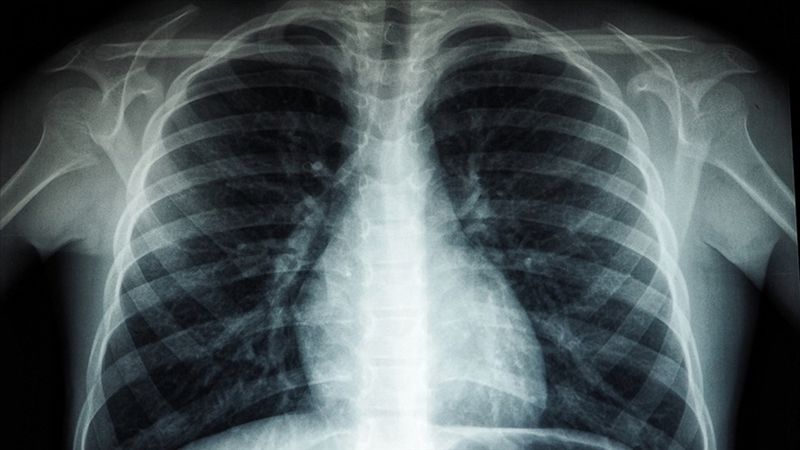

Akciğerde kalsiyum birikirse (kalsiyum oksit, kalsiyum karbonat, kalsiyum sülfat gibi kimyasallara uzun süreli maruz kalınan mesleklerde) akciğer filminde beyaz lekelenmeler görülür.